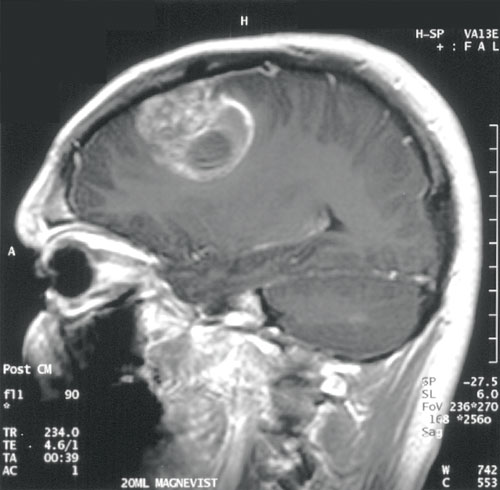

brain_tumor